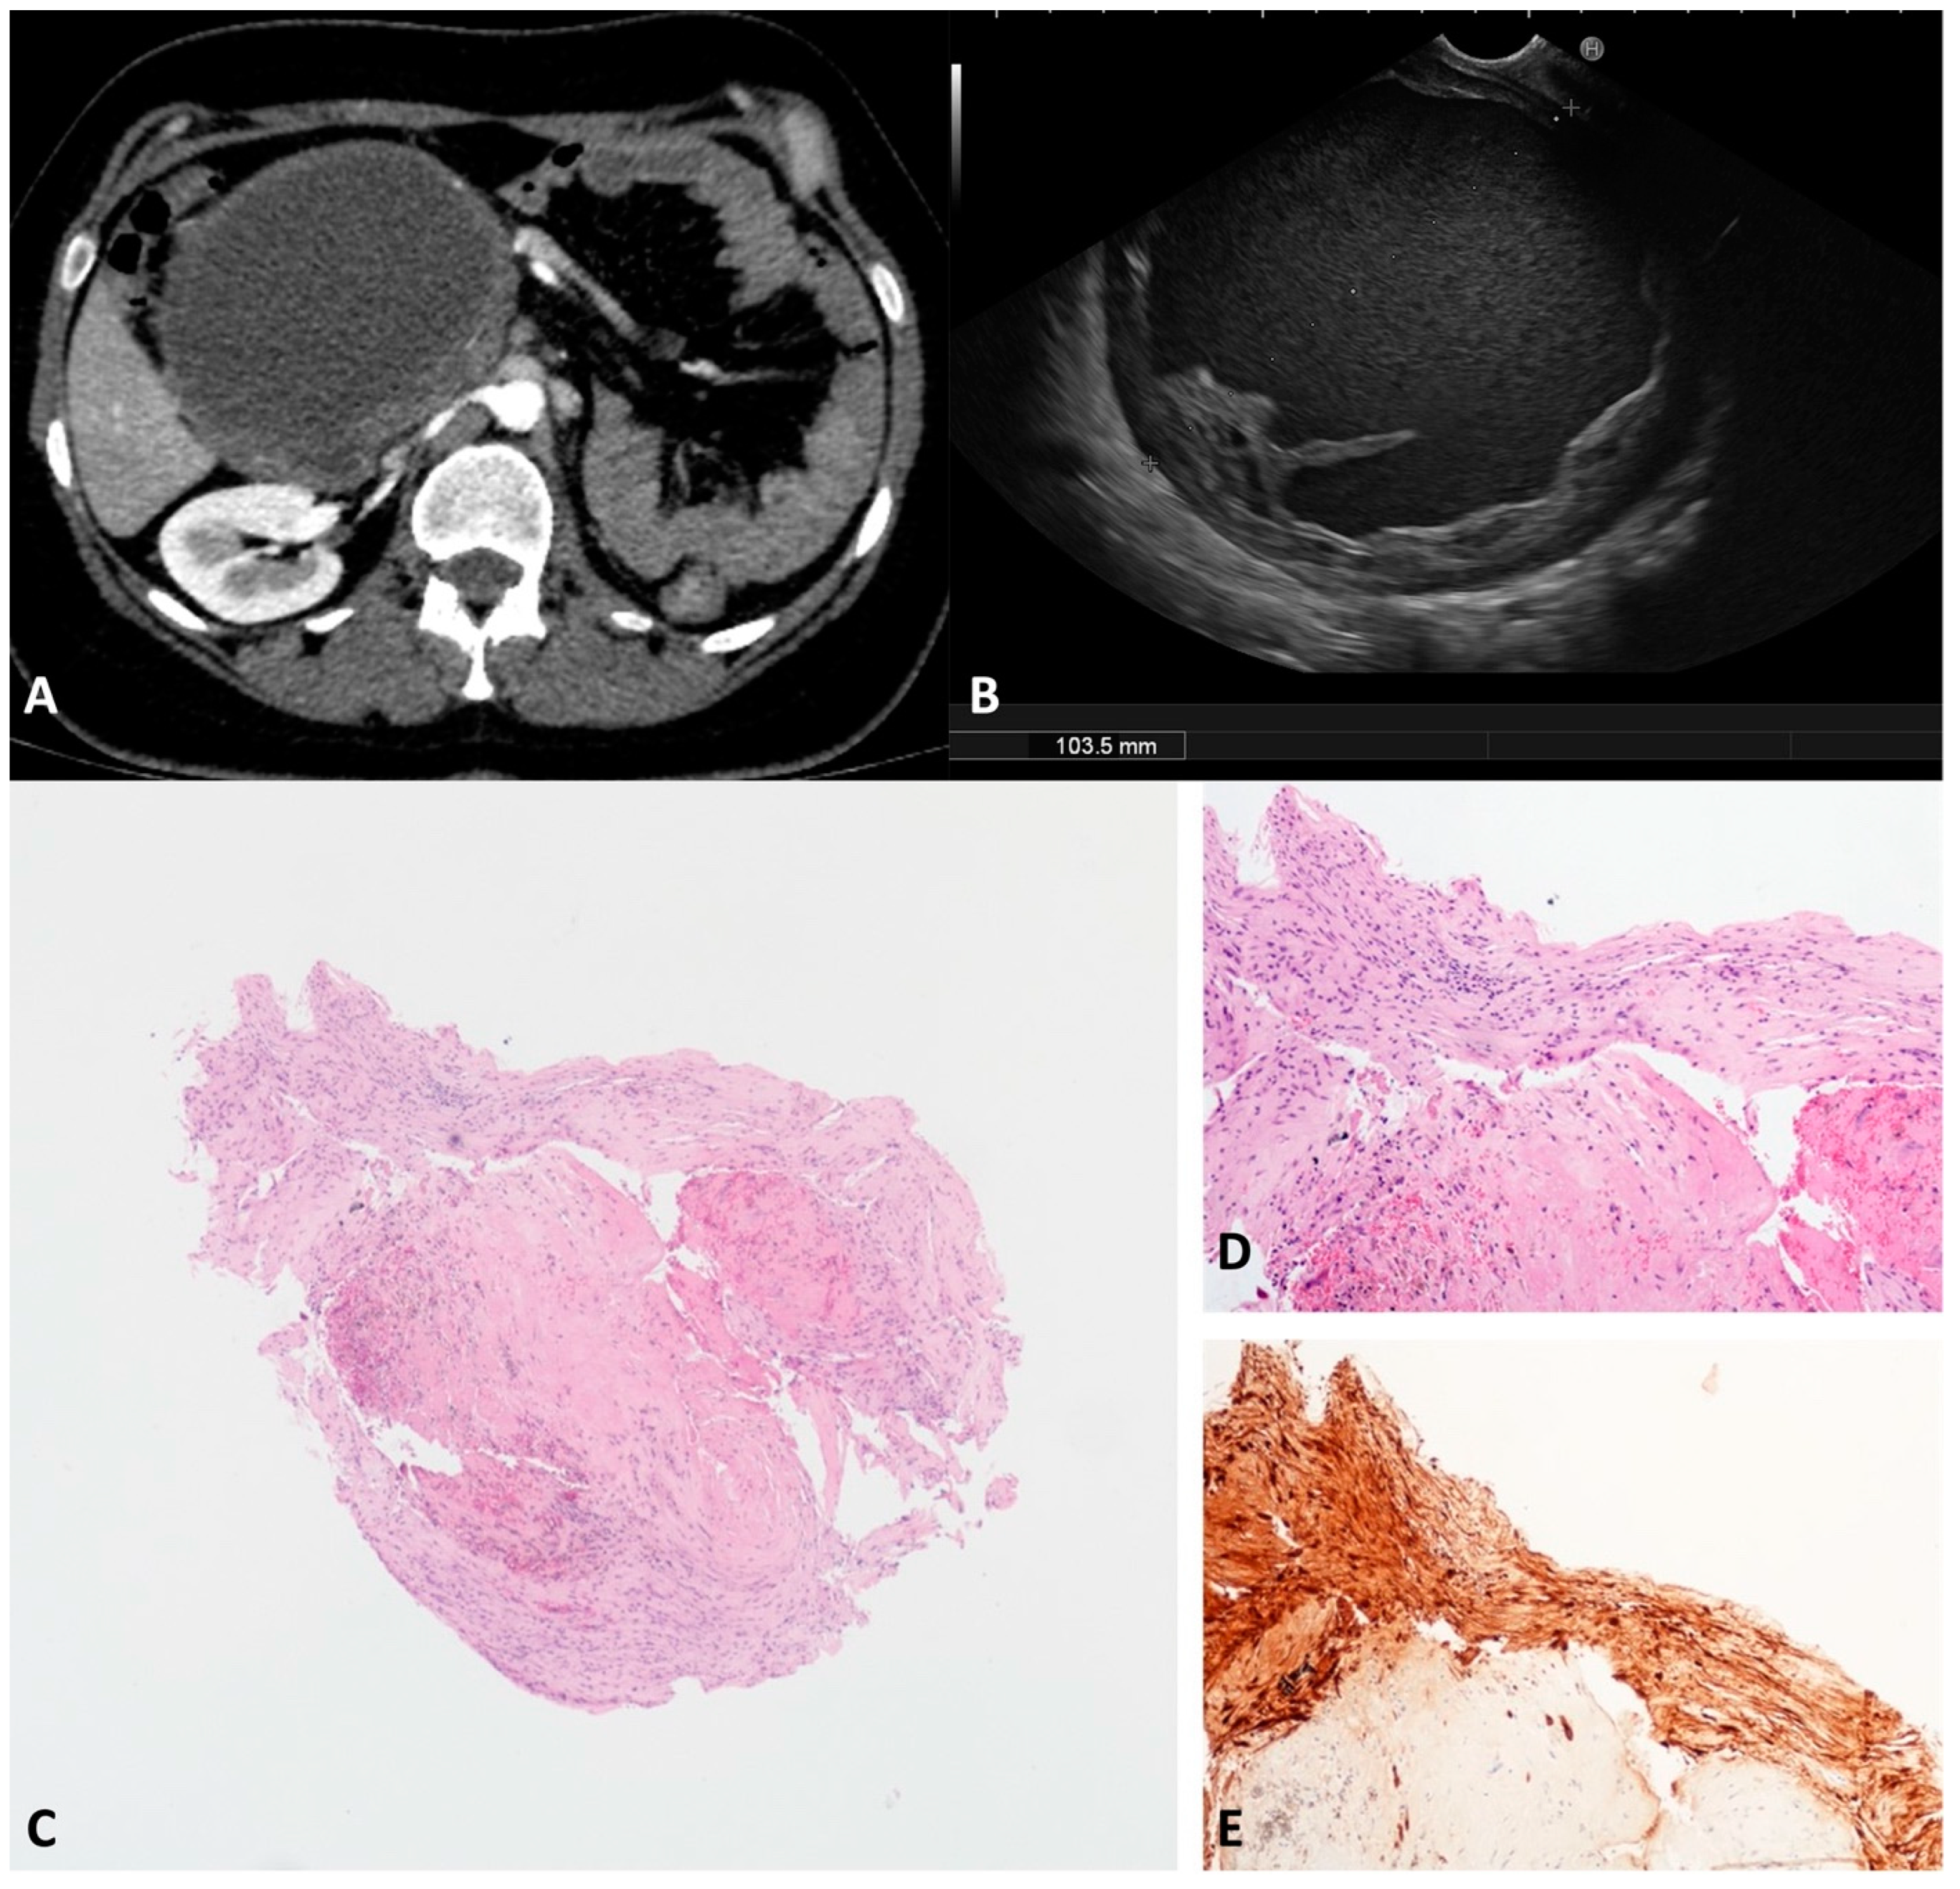

SMCs, previously called “mucinous non-neoplastic cysts”, represent an emerging subset of PCLs, whose preoperative differential diagnosis from the well-known mucinous neoplasms (MCN and IPMN) remains very challenging. Despite the shared mucin-producing cells and elevated cyst fluid CEA levels, SMCs do not have malignant potential and can be differentiated from mucinous neoplasms by the lack of ovarian-type stroma, the absence of atypia, and no communication with the ductal system []. In our series, two SMCs, 18 mm in the tail and 40 mm in the head, were diagnosed with TTNB (Figure 7), the last being confirmed in the surgical specimen after duodenopancreatectomy.

Figure 7.

Simple mucinous cyst. The whole fully mounted section of the cyst wall forceps biopsy (A). At higher magnification, the thick fibrous cist wall is lined with a monolayer of mucinous epithelial cells, without atypia (B). Hematoxylin–eosin original magnification ×40 (A), ×200 (B).

In our series, two middle-aged males presented a BC; one had a 60 mm intrapancreatic cyst located in the tail, and one had a peripancreatic 70 mm cyst located between the pancreas, left adrenal gland, posterior gastric wall, and diaphragm pillar.

Both the cysts were unilocular, thin-walled, and filled with a “starry sky” appearance due to multiple floating hyperechoic spots with comet-tail artifact (Figure 8A). According to the histology, the specimens were composed of a fibrous smooth muscle wall covered with a monolayer of “respiratory-type” epithelium with ciliated columnar cells and interspersed mucinous cells (Figure 8B–D). On the surgical specimens, the diagnosis was confirmed by the presence of seromucinous bronchogenic glands beneath the ciliated epithelium lining the cyst.

Figure 8.

Bronchogenic cyst. Typical appearance of bronchogenic cyst on endoscopic ultrasound. The content of the cyst is similar to the liver parenchyma, with multiple white spots with a comet-tail artifact (A). The cyst wall biopsy shows a thick layer of eosinophilic, dense, hypocellular tissue beneath the pseudostratified epithelium (B). The epithelium lining the cyst wall is composed of ciliated and goblet cells (C). The subepithelial connective tissue is rich in smooth muscle fibers, which are Calponin-positive (D). Hematoxylin–eosin original magnification ×100 (B), ×400 (C); Calponin original magnification ×100 (D).